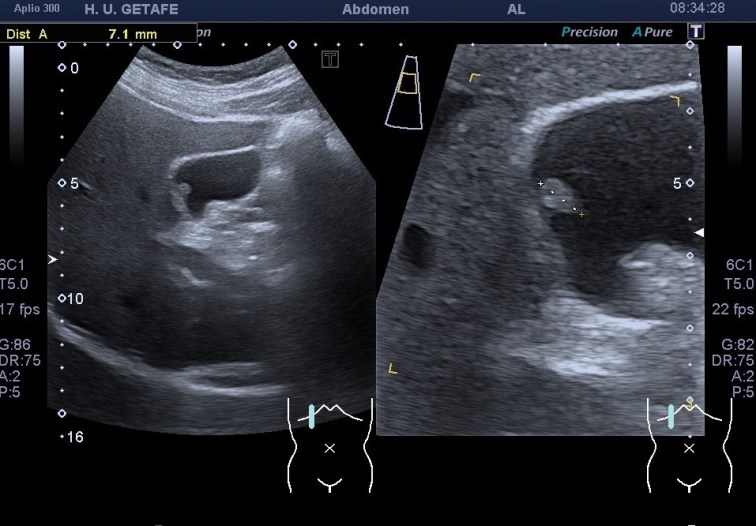

283. Pólipo vesicular. Zoom.

Son estructuras redondeadas pegadas a la pared vesicular hiperecogénicas. Normalmente única, pueden aparecer en número variable lo que se conoce como una poliposis vesicular

No presentan sombra posterior.

No se mueven al cambiar de posición al paciente.

El estudio del pólipo tras su localización se realiza en dos proyecciones, variando al paciente de posición para ver si se mueve. Ponemos doppler, tanto color como modo angio, con el objetivo de demostrar un vaso en el interior del pólipo, que lo delataría como una estructura de aspecto maligno y debería ser valorado por el radiólogo y por el cirujano convenientemente. Por eso ajustar el doppler es muy importante en este caso también.

Medimos para hacer seguimiento de la lesión si se requiriese así. Aplicamos zoom para estudiarlo detalladamente, a mi me encantan las imágenes en este Canon. El Zoom es muy bueno y el estudio del pólipo gana muchísimo. Hablando del Zoom…

Como muy bien puedes observar el caso es bastante anodino, las imágenes te las he puesto y son la excusa para explicarte el uso del Zoom. Habitualmente es un ajuste ecográfico que no usamos en exceso, solo puntualmente, puede pixelar en exceso la imagen, como cuando hacemos una foto con nuestro móvil y la ampliamos con el gesto de nuestros dedos…pixelamos la imagen, perdemos resolución, pero lo nuevos equipos, ganan en esto también y con las sondas de baja frecuencia podemos conseguir imágenes muy bonitas de alguna ecoestructura pequeña y que nos interese medir bien, y este caso me resultó muy plástico y te lo quería explicar. Repasamos el concepto de pólipo vesicular y lo enlazamos con el uso del zoom.